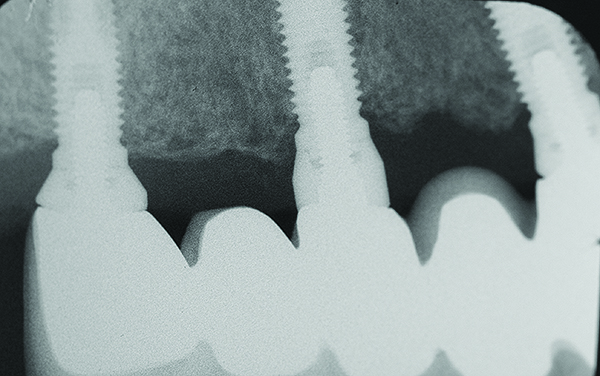

Fig 7 through Fig 14. Periapical radiographs of a 62-year-old woman who received a fixed porcelain-fused-to-metal reconstruction supported by abutments by internally connected dental implants. Fig 7 through Fig 10 are at initial prosthesis placement: mandibular site Nos. 30 and 29 (Fig 7); mandibular site Nos. 26, 25, and 23 (Fig 8); mandibular site Nos. 23 and 21 (Fig 9); mandibular site Nos. 21 through 19 (Fig 10). Fig 11 through Fig 14 are 11 years later (2013) and show excellent preservation of the vertical bone levels around the implants: mandibular site Nos. 30 and 29 (Fig 11); mandibular site Nos. 26 and 25 (Fig 12); mandibular site Nos. 25 and 23 (Fig 13); mandibular site Nos. 20 and 19 (Fig 14). It is interesting to note that in the mandibular right posterior quadrant there is a matched pair, ie, an external hex dental implant (No. 30) adjacent to an internally connected dental implant (No. 29). The bone levels around each of these designs are well-preserved at the 11-year follow-up.